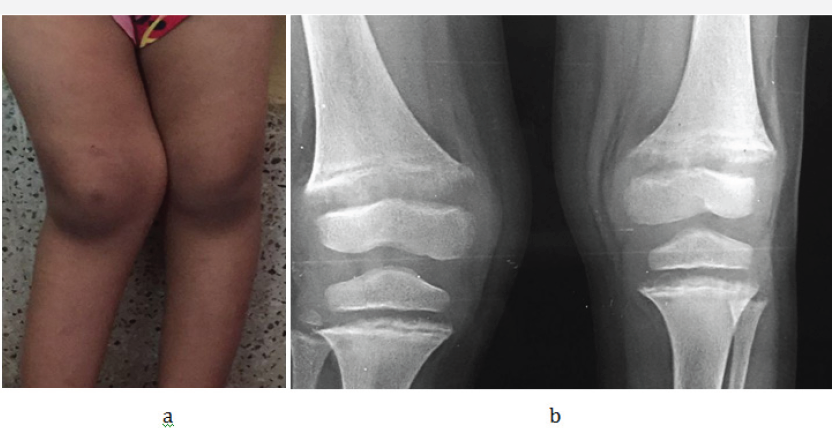

Bowing deformities and knock knees are common in the lower extremities (Figure 3a-3c).

Figure 3 a & b: 6F Rickets, a- Clinical knock knee, b- radiograph knees.

Figure 3 c: Rickets with bowed legs